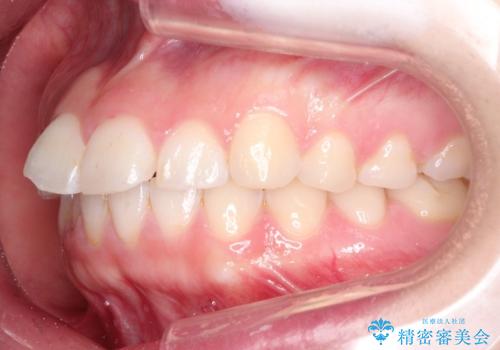

【インビザライン】前歯が出ているのを治したい

- 前歯が出ていることを主訴に来院されました。

前歯の突出感が改善され、満足していただきました。